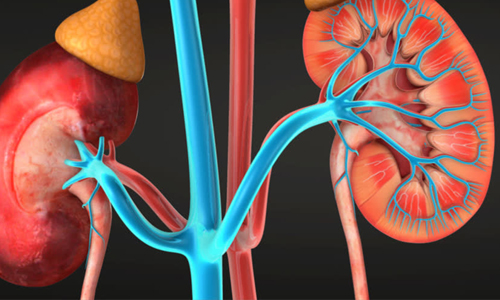

Urology

The Urology department offers comprehensive Urological service (Both Medical & Surgical Intervention) to diagnose and treat stone disease, incontinence, inflammation and various other urinary difficulties. All kind of endoscopic surgeries for stone and enlarged prostate removal are available here. The hospital is leading centre in Amritsar for carrying out PCNL, URS, TURP, OIU, TURBT etc. with the highly skilled Top Urologist In Amritsar.

In the field of kidney, prostate and bladder cancer the center is renowed and have been carrying out advanced oncological surgeries for the kidney cancers like—radical nephrectomy, partial nephrectomy and Rad neph with IVC thrombus extraction. The hospital also offers reconstructive surgeries like—pyeloplasty and advanced urethral stricture surgery. Karam Hospital comes under the best urologist in Amritsar because they have the best urologist doctor in their hospital.